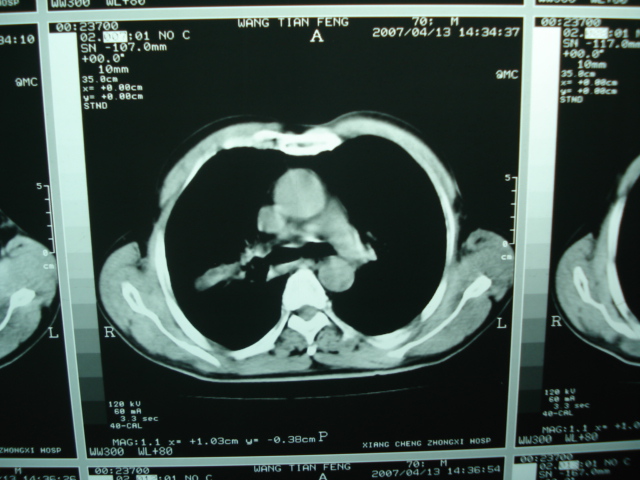

以下是引用狙击手在2007-4-18 20:17:00的发言:[br]原:2007/1/22号ct片:右肺上叶可见片状、云雾状高密度影,右肺上叶后段可见三角形高密度影,尖端指向肺门,右肺上叶后段支气管壁不规则增厚,管腔不规则增厚,纵隔未见肿大淋巴结.[br] 今ct:右肺上叶片状影增大,右肺上叶后段不张及右肺上叶后段支气管壁不规则增厚未见变化,右肺下叶背段支气管壁不规则增厚.[br] 如果考虑肺结核,但从临床证据看竟然没有一项支持肺结核,不知患者是否已经过正规抗结核治疗。没有的话,3个月了前后片看起来变化不大,似乎有不太符合肿瘤征象,不知患者是否抗炎治疗过,下叶支气管增粗还是要高度警惕,同意楼主意见,将常规病理,生化检查再做一遍。[br]

以下是引用狙击手在2007-4-18 20:17:00的发言:[br]原:2007/1/22号ct片:右肺上叶可见片状、云雾状高密度影,右肺上叶后段可见三角形高密度影,尖端指向肺门,右肺上叶后段支气管壁不规则增厚,管腔不规则增厚,纵隔未见肿大淋巴结.[br] 今ct:右肺上叶片状影增大,右肺上叶后段不张及右肺上叶后段支气管壁不规则增厚未见变化,右肺下叶背段支气管壁不规则增厚.[br] 如果考虑肺结核,但从临床证据看竟然没有一项支持肺结核,不知患者是否已经过正规抗结核治疗。没有的话,3个月了前后片看起来变化不大,似乎有不太符合肿瘤征象,不知患者是否抗炎治疗过,下叶支气管增粗还是要高度警惕,同意楼主意见,将常规病理,生化检查在做一遍。[br]